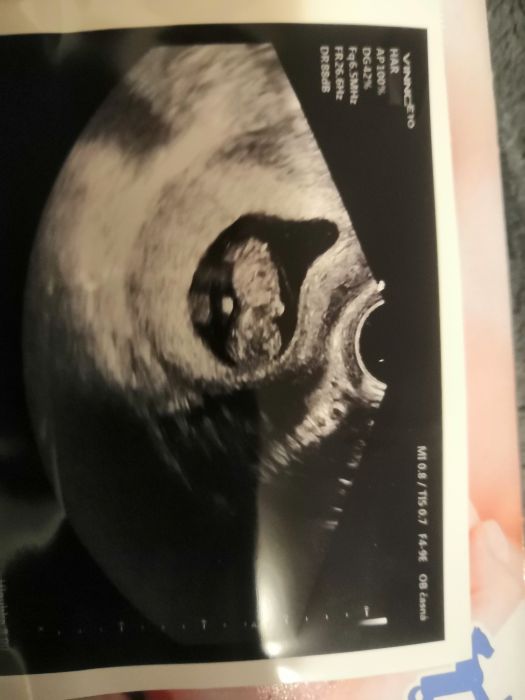

Tak já dnes byla v poradně.. mám nového gynekologa.Predchozí 3těhu u jiného lékaře celkem 3-4ultrazvuky.Tento mi ho dělá pokaždé v poradně.Někde jsem četla je to není dobré pro mimi.Slyšela jste některá o tom něco?A jak to máte vy?Jinak dnes ho měřil a bylo větší 12+6 přitom jsem 12+1.Vrtělo se zprava doleva..tak to treba bylo tím.Holky a na jaký jdete screning?Obyčejný nebo si necháte udělat ty lepší testy?Já mám v plánu rozšířený Harmony..výsledky jsou 99.8%.Doktor říkal.. ze když to vyjde dobře..nebude mě posílat v tom 16tt na tripletest.Chtěla bych udělat 3D ulz..jesťě jsem ho nikdy neměla.Teď jsem se dívala na netu na obrázky z 13tt a jsou úzasný.Jak to máte v plánu vy??Přikládám foto mimíska z dneška?

Já jdu zítra na krev a 5.2. na velký screening. Takže krev je a už mi dělá vždy. Mám i z každého fotku. Ale říkal že ty tisknutí jsou méně kvalitní, že je mám fotit telefonem. Nemyslím si že by to bylo úplně nezdravé pro mimi. Když jdu sednout s manželem do hospody je to určitě více nezdravé. A 3d ultrazvuk asi nechci moc se mi to nelíbí. Přijde mi to zbytečný. A Kači a ty jsi mi ukradla fotku dítěte že ? Teda já jsem ofiko 12 +3 ale podle už 10+3 těším se na screening. Zle mi je stejně zle ale už se na malého těšíme a říkáme to postupně rodině. Doufám že to bude holčička mám šílený akné.. Tak uvidíme. Myslím na vás holky. Jste dobrá podpora.. Moc tady kamarády nemám. Posílám vám fotky malého flíčku